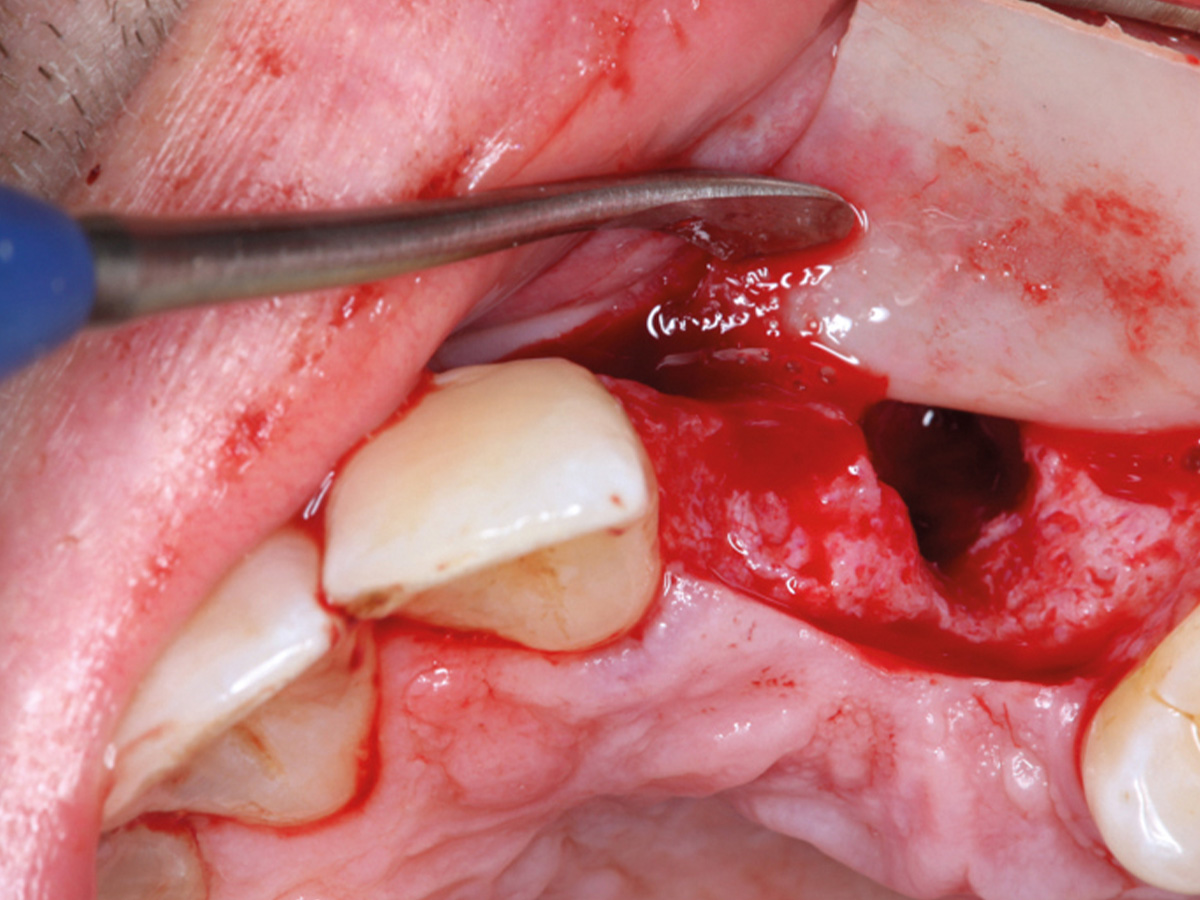

Abbildung 9

Retromolarer Eigenknochengewinn.